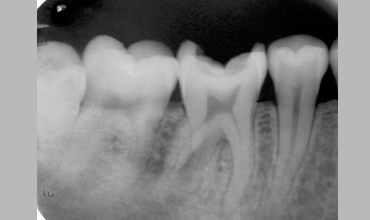

Management Of Radix Entomolaris In Mandibular First Molar